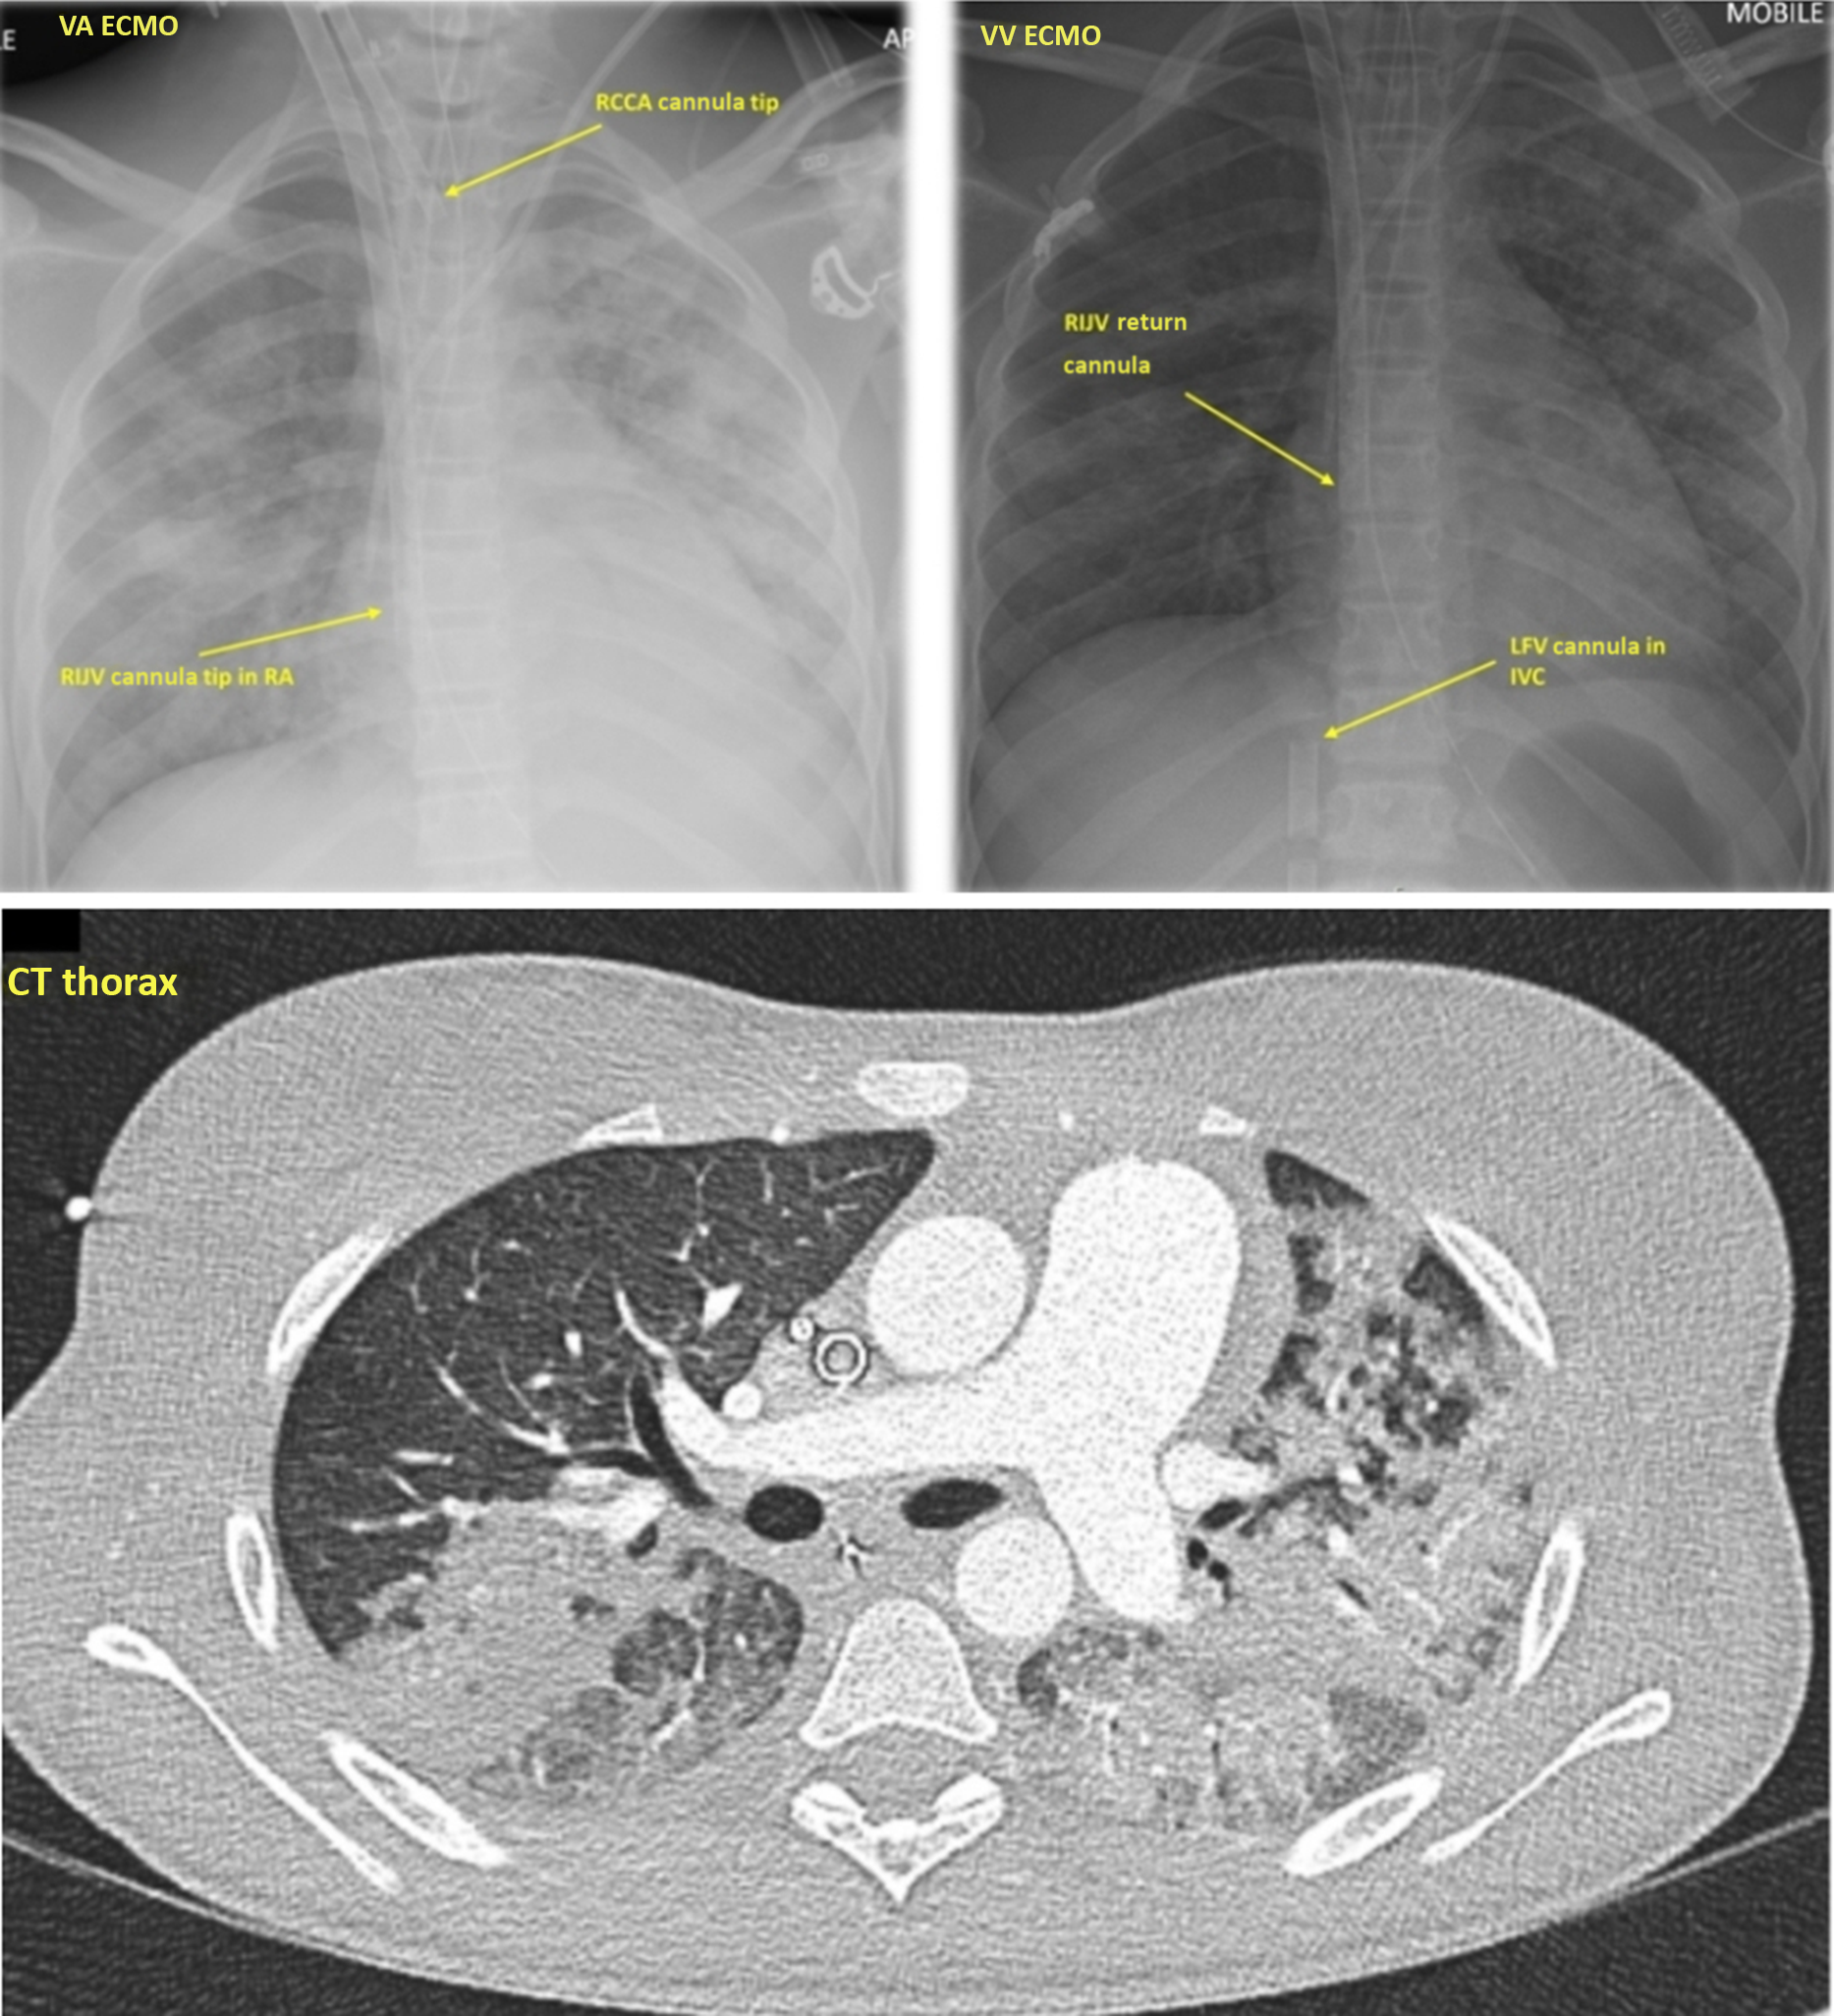

Figure 2. CXR showing VA ECMO with RCCA cannula tip and RIJV cannula tip in RA, VV ECMO with RIJV return cannula and LFV cannula in IVC. VA = veno-arterial; ECMO = extracorporeal membrane oxygenation; RCCA = right common carotid artery; RIJV = right internal jugular vein; VV = veno-venous; LFV = left femoral vein; IVC = inferior vena cava.

In view of the rapidly worsening cardiovascular instability, and following multidisciplinary team discussion, we decided to put the patient on veno-arterial extracorporeal membrane oxygenation support through cannulation of neck vessel. The right common carotid artery was cannulated with a 15-Fr Bio-Medicus NextGen femoral arterial cannula (Medtronic Inc.) which was directly inserted with the tip positioned at the proximal brachiocephalic trunk. The right internal jugular vein was subsequently cannulated with a 21-Fr Bio-Medicus NextGen jugular venous cannula (Medtronic Inc.) with its tip positioned in the middle of the right atrium (Fig 2). A flow of 3 L/minute was achieved and features of shock resolved. Bilateral cerebral near-infrared spectroscopy monitoring was stable at 85–88%. The patient was anticoagulated with heparin infusion at 40 units/kg/hour targeting a high anti-Xa level (0.5–1.0 IU/mL) to prevent thrombosis as d-dimers and fibrinogen were high.

In combination with levosimendan (inodilator) 0.05–0.1 mcg/kg/minute infusion over 24 hours on day 2, cardiac function gradually started to recover, with improved left ventricular ejection and adequate decompression on echocardiography. Despite therapeutic anticoagulation, a thrombus in the right atrium related to the tip of the venous cannula was seen on echocardiogram, which raised the concern of systemic thromboembolism. Following improved cardiac function, but the transient development of hypoxia on trial weaning of veno-arterial extracorporeal membrane oxygenation in conjunction with widespread pulmonary consolidation, the patient was converted to veno-venous extracorporeal membrane oxygenation on day 5. This was achieved following the insertion of a 21-Fr left femoral vein access cannula, with the tip positioned in the inferior vena cava, and the use of the existing right internal jugular vein 21 Fr as a return cannula (Fig 2).